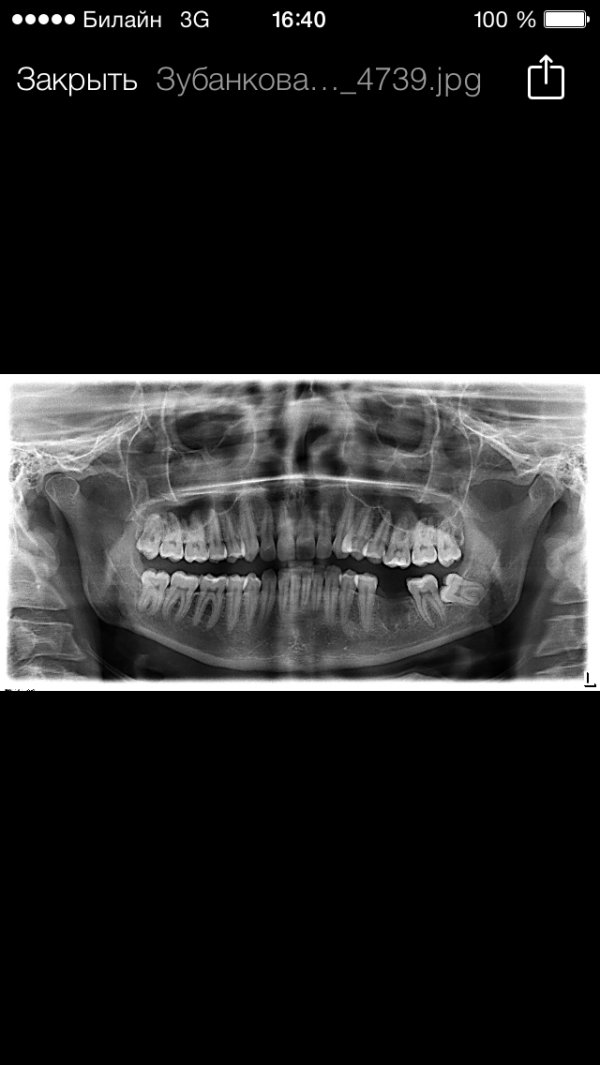

Удален шестой зуб резорциновый. Сделана мной ортопантомограмма. На снимке видно, что костная ткань, где были корни зуба, не восстановилась.

Подскажите, пожалуйста, срок восстановления костной ткани и что может послужить не восстановлению моей костной ткани? Возможна ли в дальнейшем имплантация?

Срок восстановления костной ткани зависит от степени травматичности удаления, но как правило, от 3 - 6 месяцев. Выложите мне снимок, я вам все расскажу.